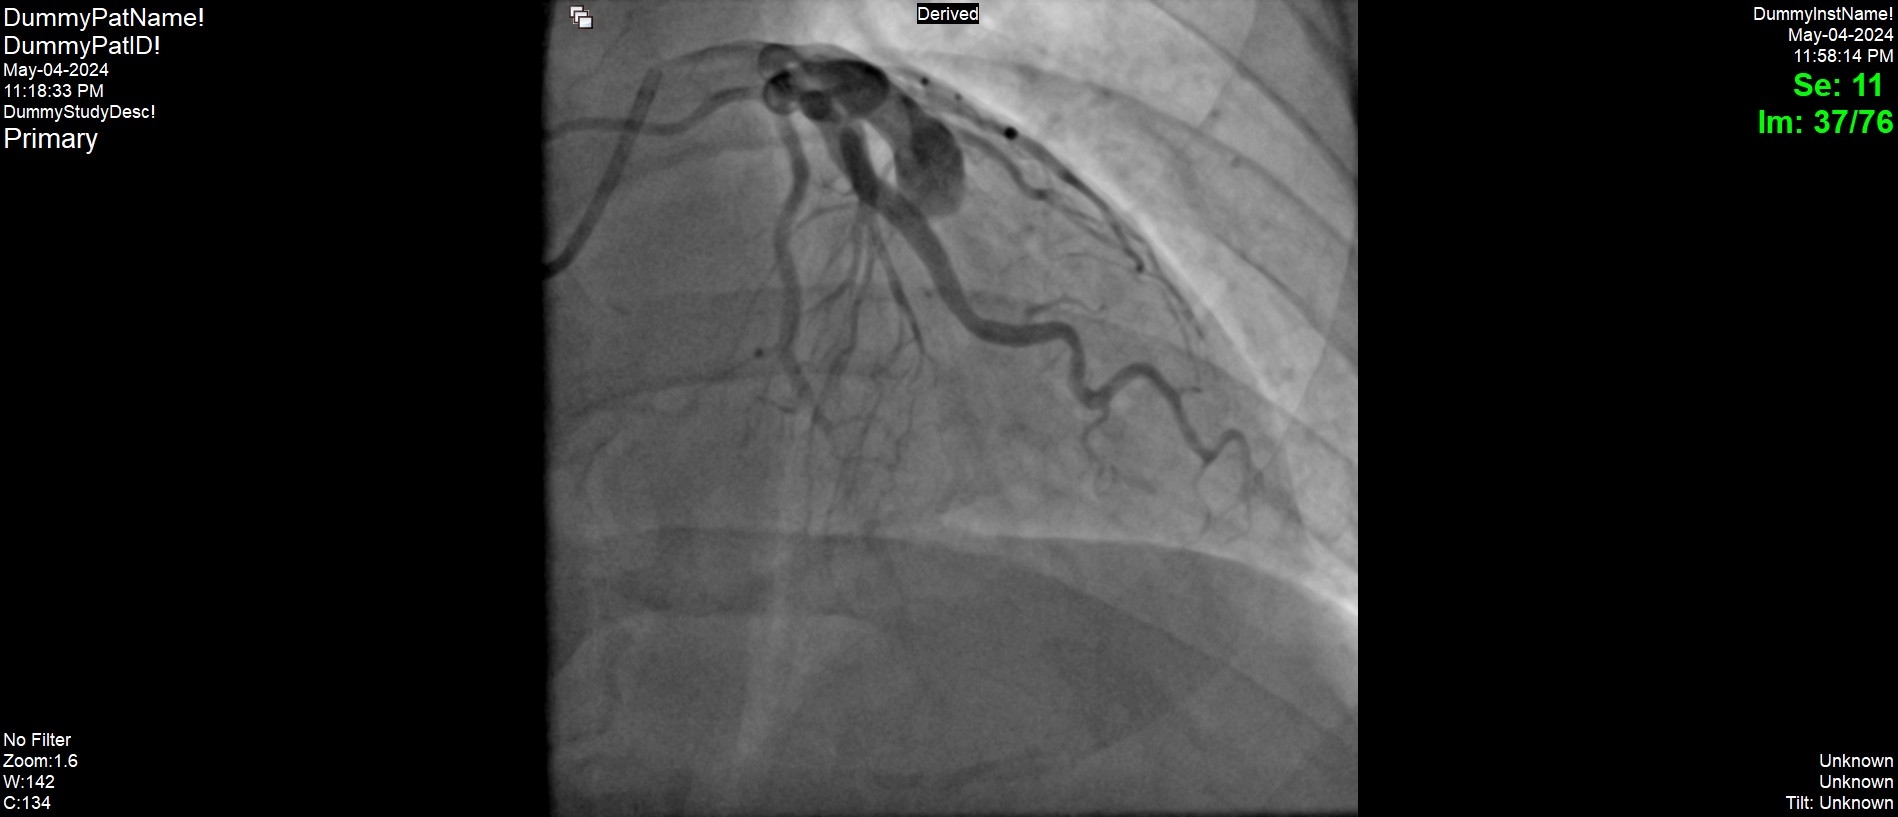

ST Elevation Myocardial Infarction in the Setting of Severe Ectasia and Aneurysm of the Left Anterior Descending Coronary Artery.

An emergent left heart catheterization and coronary angiogram was performed which revealed a 100% thrombotic occlusion of the mid LAD as well as severe ectasia of the proximal vessel. There was mild ectasia of the left circumflex and right coronary arteries without any significant stenosis. There were no collaterals to the distal LAD consistent with an acute presentation. At the level of the occlusion (mid LAD), there was an aneurysm measuring up to 10 mm in diameter by angiography. Intravenous eptifibatide was administered with the continuation of IV heparin. The thrombotic occlusion was managed medically with a plan to repeat angiography in 24-48 hours. Transthoracic echocardiography revealed a preserved left ejection fraction at about 55-60% with mild hypokinesis of the apex. Repeated angiography in 48 hours revealed a mostly patent LAD with diffuse TIMI 2 flow and sub occluded distal LAD at the apex. He was discharged home with dual antiplatelet therapy, a statin, and a beta blocker. Two weeks later he was seen on outpatient setting and his medications were transitioned to Rivaroxaban and clopidogrel

Large LAD aneurysms are not common and they carry long term complications which includes thrombosis (as seen in our patient), fistula formation, and rupture. Management of this condition is still challenging as there are no standardized management guidelines.